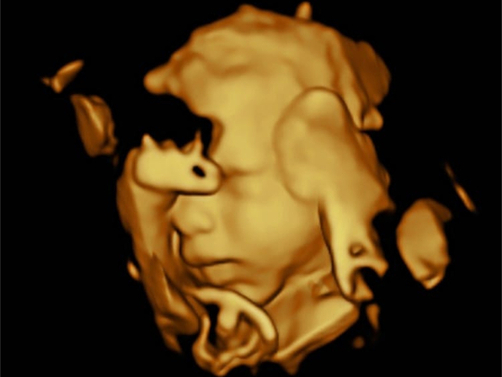

3D / 4D

Facial feature scan